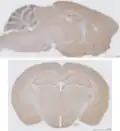

Sectional planes of the brain -

Sagittal section (top) vs. coronal section (bottom) of a mouse brain